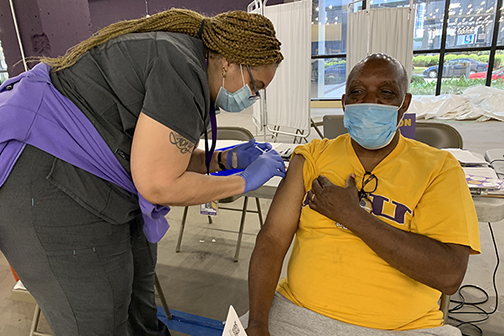

LSU Health Funded to Support Community Health Workers for Pandemic Response

LSU Health New Orleans has been awarded $2,314,161 by the Centers for Disease Control and Prevention and the Office of Minority Health to support community health workers in New Orleans, throughout Louisiana and nationally. The funding will provide the knowledge and skills to support the COVID-19 public health response and move toward health equity. More

LSU Health’s Millet Tapped for National COVID Vaccination Initiative

Clair Millet, DNP, APRN, PHCNS-BC, Director, Faculty Development, Continuing Nursing Education & Entrepreneurial Enterprise at LSU Health New Orleans School of Nursing, has been appointed to the Nurse-Led Vaccine Confidence Advisory Committee of the National Nurse-Led Care Consortium. More

LSU Health COVID Vaccination Clinic Taking Walk-Ins Wednesday

LSU Health New Orleans’ COVID Vaccination Clinic on the first floor of 2020 Gravier Street is accepting walk-ins Wednesday, April 21, 2021, from 8:30 a.m. until 3:00 p.m. for the first dose of the Pfizer vaccine. Appointments will not be necessary. LSU Health New Orleans can vaccinate individuals 16 years of age and older. More